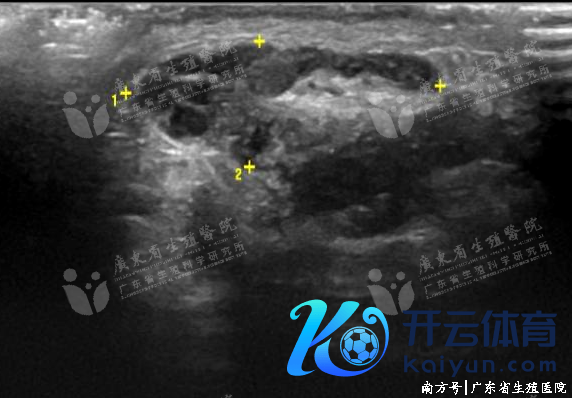

获取性输精管缺如

最常见的原因是输精管结扎术,其次还有生殖说念感染(如淋球菌感染、结核杆菌感染等)、医源性毁伤(如腹股沟疝修补术、精索静脉结扎术、鞘膜切除术等)、输精管肿瘤等。输精管炎性梗阻多覆没附睾梗阻,多因泌尿系及男性生殖系统的感染播散所致,输精管炎常与附睾炎同期存在。超声上可见输精管管壁增厚,回声增强,管腔彭胀,内可见密集点状回声浮动,部分摊腔内可见斑片状钙化灶。

输精管睾丸段炎性梗阻